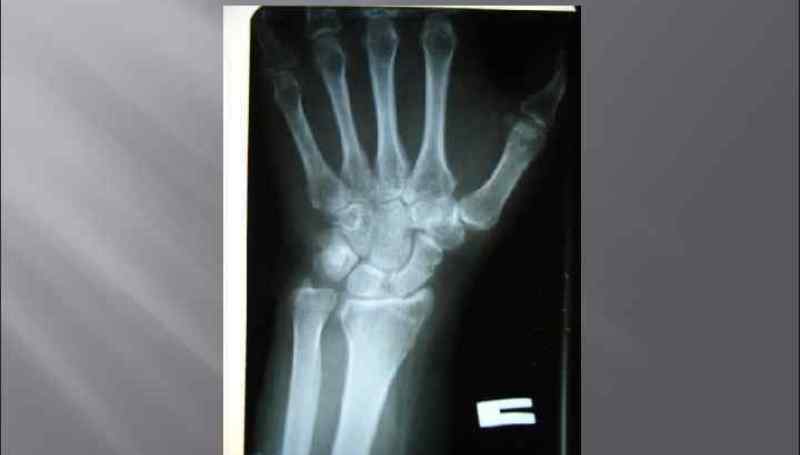

Также существует перелом шиловидного отростка локтевой кости, при котором на рентгеновском снимке можно увидеть деформацию контуров конца локтевой кости.

Диагностика перелома

На начальном этапе врач проводит сбор анамнеза заболевания, во время общения с пациентом уточняет детали происшествия и время падения. Затем осуществляется осмотр, после которого пострадавший направляется на рентгенографию лучезапястного сустава в двух проекциях: прямой и боковой.

Если требуется более подробная информация о состоянии мягких тканей, может быть назначена компьютерная томография или ультразвуковое исследование.